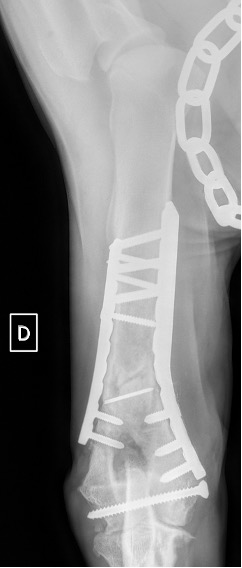

Notre préférence va vers le placement de deux plaques humérales : une médiale de la plus grande taille possible et l’autre latérale, généralement d’une taille inférieure à la première. Dans l’exemple 1 (chat européen), une plaque de 2 mm est utilisée médialement et une plaque de 1,5 mm latéralement. Dans l’exemple 2 (chien Malinois), une plaque de 3,5 mm est utilisée médialement et une plaque de 2,7 mm latéralement.

Exemple 2 :

Figure 5 : Post-Op Immédiat